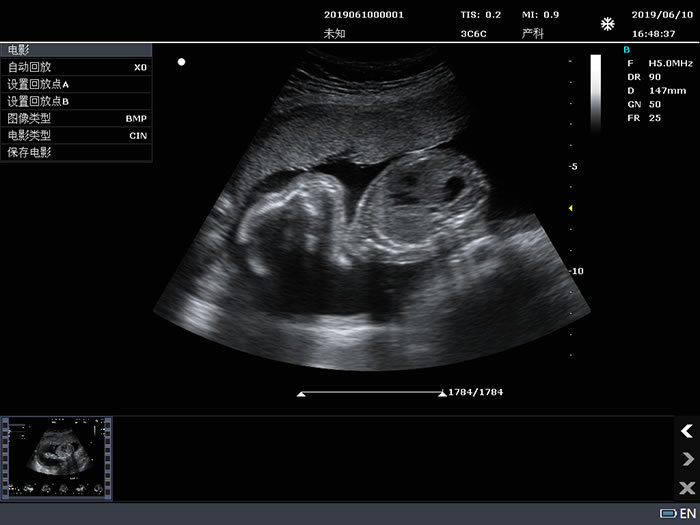

产科B、PW模式应用测量:包括全面的产科径线测量、体重、单胎孕龄及生长曲线、羊水指数、胎儿生理评分测量等